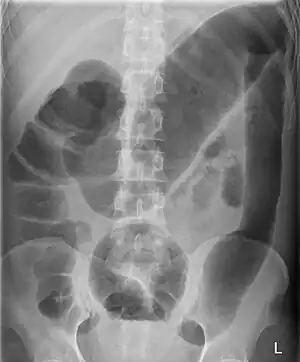

Megacolon is an abnormal dilation of the colon (also called the large intestine).[1][2] This leads to hypertrophy of the colon.[2] The dilation is often accompanied by a paralysis of the peristaltic movements of the bowel. In more extreme cases, the feces consolidate into hard masses inside the colon, called fecalomas (literally, fecal tumor), which can require surgery to be removed.

A human colon is considered abnormally enlarged if it has a diameter greater than 12 cm[3] in the cecum (it is usually less than 9 cm[4]), greater than 6.5 cm[3] in the rectosigmoid region and greater than 8 cm[3] for the ascending colon. The transverse colon is usually less than 6 cm in diameter.[4]

Diagnosis is achieved mainly by plain and contrasted radiographical and ultrasound imaging. Colonic marker transit studies are useful to distinguish colonic inertia from functional outlet obstruction causes. In this test, the patient swallows a water-soluble bolus of radiocontrast agent and films are obtained 1, 3, and 5 days later. Patients with colonic inertia show the marker spread throughout the large intestines, while patients with outlet obstruction exhibit slow accumulations of markers in some places. A colonoscopy can also be used to rule out mechanical obstructive causes. Anorectal manometry may help to differentiate acquired from congenital forms. Rectal biopsy is recommended to make a final diagnosis of Hirschsprung disease.[12]